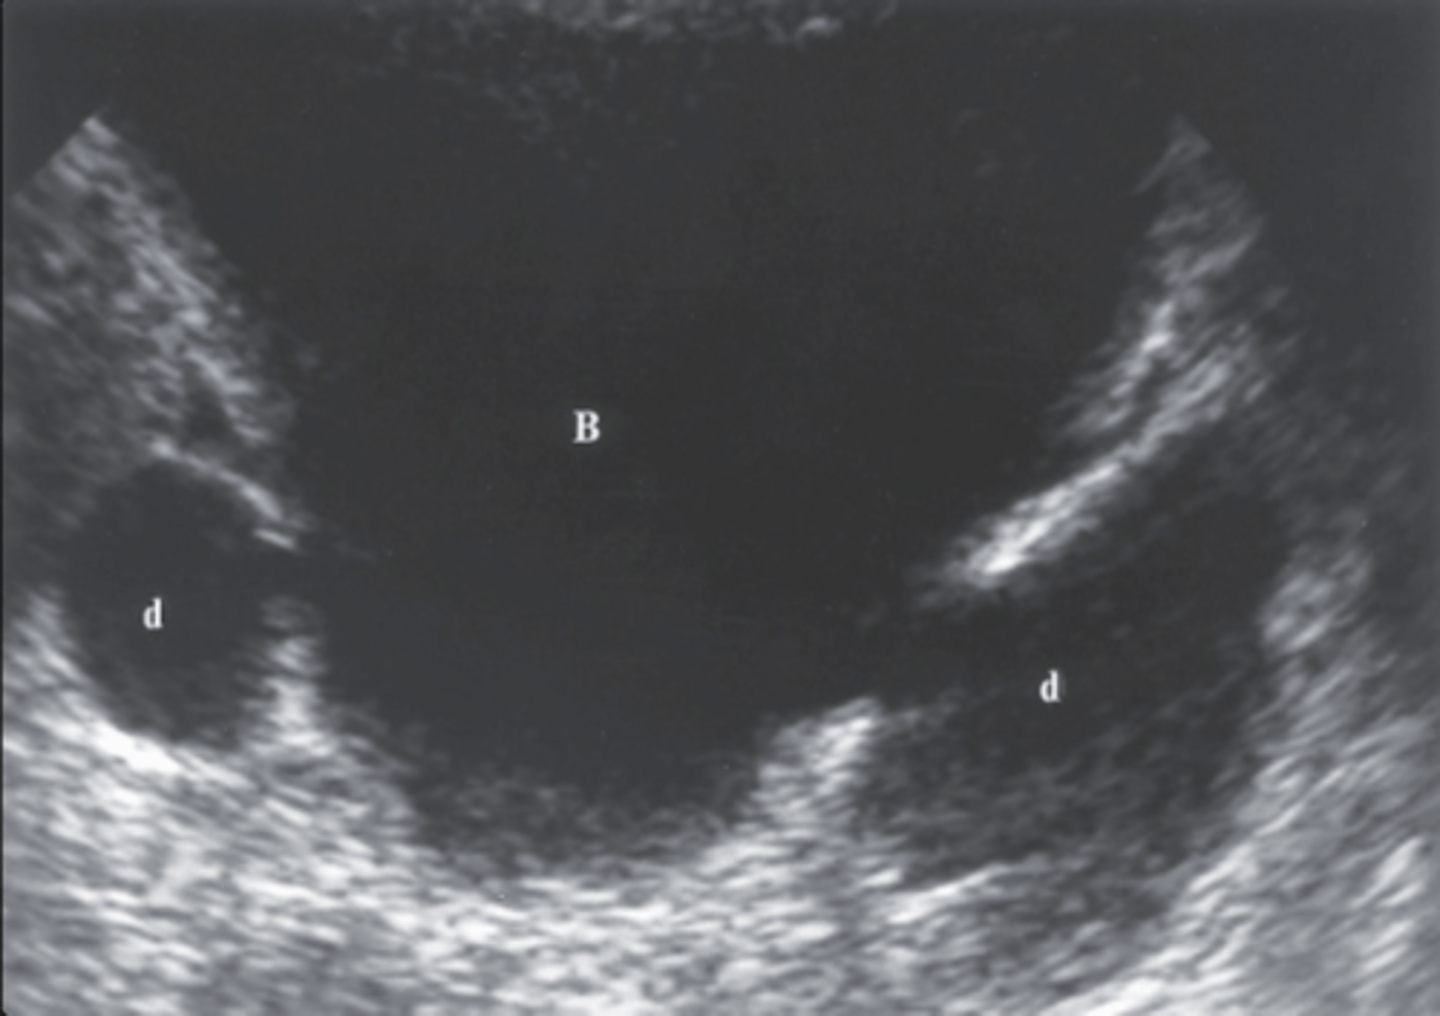

19. Figure 7-45 is an image of a 61-year-old male with gross hematuria. Which of the following would be the most likely diagnosis for the mass (M) noted in this transverse image?

a. Renal adenoma

b. TCC

c. Renal hamartoma

d. Renal hyponephroma